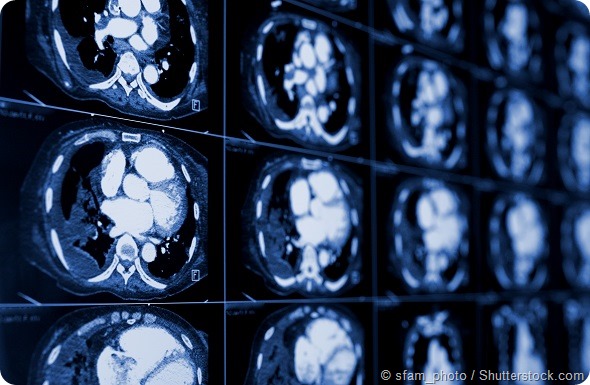

ILD is the result of inflammation and scarring in the lungs, and is one of the leading causes of death among people with systemic sclerosis. Gastrointestinal, heart and kidney involvement can also lead to substantial morbidity and mortality.

The presence of inflammation and scarring (fibrosis) in the lungs can result in an accelerated and progressive decline in lung function. As lung function declines, patients become more easily short of breath and generally require more and more supplemental oxygen in order to maintain normal oxygen levels in the blood.